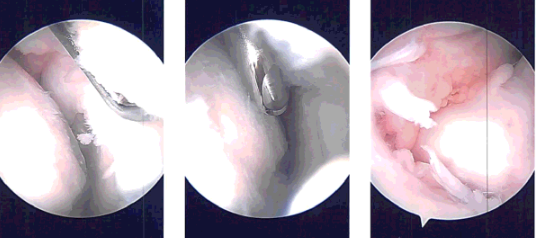

After all of shaving, the camera was introduced in the patellofemoral joint where the grade 3 to grade 4 osteoarthritic changes of the trochlea were observed and abrasion chondroplasty was performed.

There were grade 2 to grade 4 osteoarthritic changes on the posterior surface of the patella which were debrided. was performed using a shaver.

Now, the scope was entered through the medial portal and the scope was entered through the medial portal and further debridement of the lateral meniscus was performed using a shaver, upfitters, back biter and left-sided biters.

After balancing the medial aspect of the lateral meniscus, the rest of the examination was performed and the findings were taken.

The knee was irrigated. Closure was done after irrigation using # 3-0 nylon; 10 cc of 0.5% Naropin with 40 mg Depo-Medrol was injected in the knee. Tourniquet was removed.